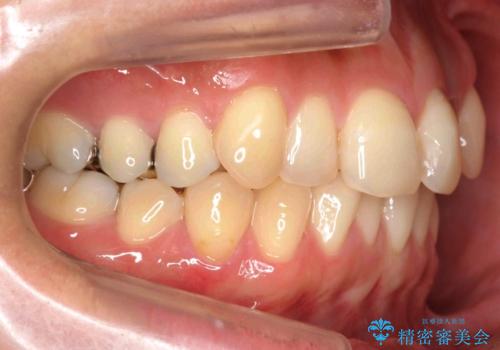

埋まっている奥歯を引っ張り出す インビザライン矯正

- 前歯のがたつきと左下の歯がうまっているとのことで、矯正治療を希望されました。

埋まっている奥歯を並べることで、その後ろの倒れ込んだ歯を整直させることができました。

引っ張り出すことはマウスピース矯正では難しい為、埋まっている歯を並べるスペース確保と、引っ張り出すのに、ワイヤーを用いた部分矯正を行なっています。

上の歯はマウスピース矯正で、奥歯を後ろに下げて、左のかみ合わせのズレを直しています。

上下とも非抜歯で並べています。

埋まっていた歯をしっかり引っ張り出すことができ、また、前歯の見た目も非常に良くなりました。

ワイヤー矯正を奥歯の部分的に行なっただけで、治療の大半をマウスピース矯正で行うことができ、非常に喜んでいただきました。